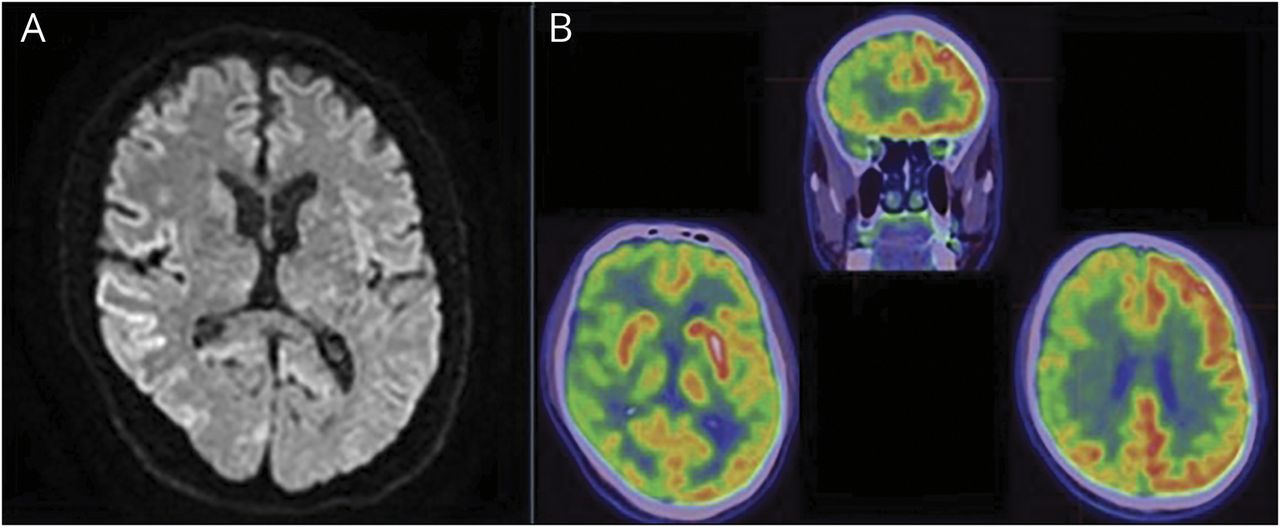

病例报告

一名58岁男性右撇子以4个月的发作性左侧无力和持续数小时的侧向排斥力就诊于神经病学门诊。首页初次就诊5个月后,患者出现进行性、持续性左侧症状,包括疼痛、步态不稳、左臂和左腿肌阵挛性抽搐。他还报告了“受限”的运动和不正常的触觉,例如,他很难确定地放下左脚,并报告说左手拿着的东西对他来说是陌生的。他没有认知障碍,他的妻子证实他的行为或性格没有变化。通过蒙特利尔认知能力评估测试,患者的认知功能得到了保留,得分为26/30。力量和主要感觉模式正常。患者左上肢和下肢持续肌阵挛抽搐,左上肢轻度失用症,左手上移(顶骨举)。二级感觉模式测试显示双侧失觉(左侧更严重)和左侧消失。他的深肌腱反射全是+2;然而,他有一种夸张的震惊反应。 His gait was wide, with uncoordinated movements on the left with abnormal posturing of his left arm while walking. A brain MRI demonstrated diffusion restriction in the right temporal, parietal, and occipital cortices (图1一个)与扩散系数明显相关,但T2 FLAIR无明显变化。回顾性检查他在疾病发作期所做的先前脑部mri,发现在相同区域的弥散加权成像(DWI)上有细微的扩散限制,这在最初的神经放射学检查中未被发现。脑电图显示右半球的背景侧化复杂δ变慢。12天后的第二次脑电图显示右半球不对称和左额-中央复合三角洲加重,右半球周期性放电,呈三相形态(图2)。PET扫描显示整个右脑半球代谢低下,包括(在较小程度上)右侧基底神经节和丘脑(图1 b)。脑脊液检查显示白细胞计数和蛋白正常,快速PCR检测显示脑膜炎/脑炎阴性。脑脊液副肿瘤和自身免疫性痴呆面板呈阴性。脑脊液神经元特异性烯醇化酶升高(45 ng/mL,正常0-30 ng/mL),总tau蛋白升高(4,853 pg/mL,正常< 0-1,149 pg/mL)。脑脊液14-3-3和RT-QuIC均呈阳性。左乙拉西坦对症治疗肌阵挛。他的智力继续迅速下降,最终发展为动态缄默症。患者在脑脊液检查结果返回1个月后和出现持续性运动症状4个月后死亡。由于缺乏家族病史或暴露于朊病毒病的医源性或饮食来源,推测他患有散发性克雅氏病(CJD),后来经尸检证实。Western blot和免疫组化分析结果显示异常朊病毒蛋白阳性,未发现有害基因突变的证据含有朊基因。